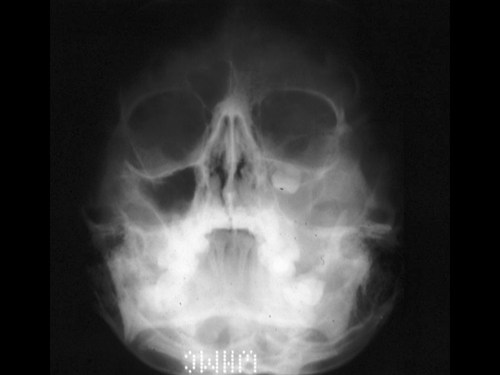

Radiology of the Case:

The sinus on the left side is opacified and contains a tooth. There does not seem to be significant destruction of the surrounding bone on this plain film.